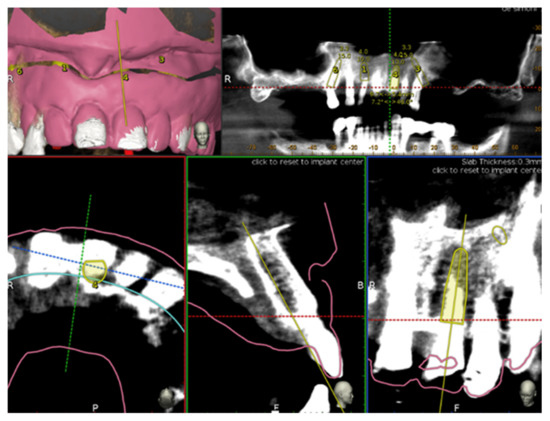

2.4. Plan

A cone beam computed tomography CBCT (Scanora3Dx, Soredex, Tuusula, Finland) and an intraoral surface scan IOS (Medit i500, Medit Corp., Seoul, South Korea) of each patient were taken. An ideal virtual wax-up of the teeth to be replaced was completed. Both the Digital Imaging and Communications in Medicine (DICOM) files (from the CBCT) and the stereolithography (STL) files (from the IOS) were merged into the Navident software (ClaroNav Inc., Toronto, ON, Canada) and overlapped semi-automatically to the residual teeth using the provided mesh-to-image registration tool.

Implants placement was then prosthetically planned utilizing the digital wax up of the missing teeth (Figure 1). As part of the planning, the surgeon selected 3–6 landmarks on hard tissue structures, typically teeth, to be used as the starting points for tracing.

Figure 1. Implant planning by using stereolithography (STL) file as reference for a prosthetic driven implantation.